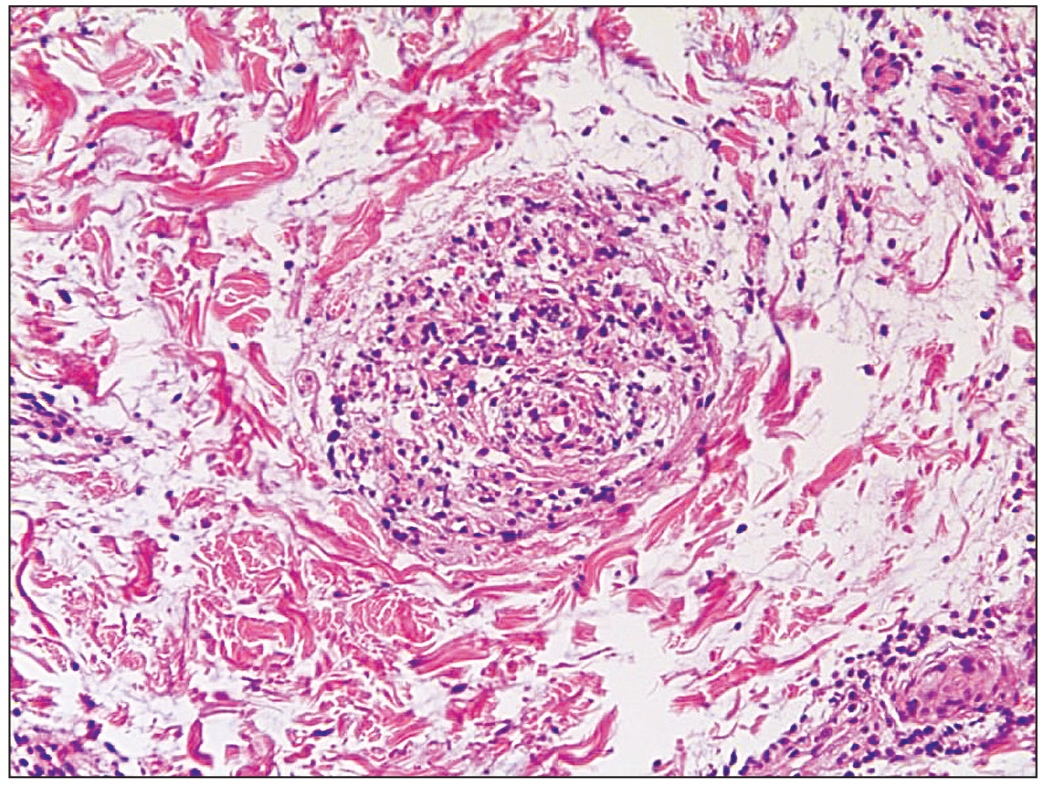

Гистологически ВП характеризуется гидропической дистрофией в эпидермисе, поражением дермы и подкожно-жировой клетчатки с обширным перисептальным и лобулярным лимфоплазмоцитарным инфильтратом, фибриноидной дегенерацией, гиалиновым некрозом жировой ткани, кальцификацией, часто – отложением муцина в дерме. Может наблюдаться периваскулярная лимфоцитарная инфильтрация с преобладанием плазматических клеток [12–14].

Результат гистологического исследования глубокой биопсии кожи: эпидермис не изменён; в дерме явления продуктивного васкулита. Инфильтрат состоит преимущественно из лимфоцитов. Клетки инфильтрата пропитывают утолщённые стенки сосудов. В подкожно-жировой клетчатке преимущественно лимфоидный инфильтрат, окружающий адипоциты, с примесью плазматических клеток. Заключение: морфология соответствует клиническому диагнозу глубокой красной волчанки (рис. 2).